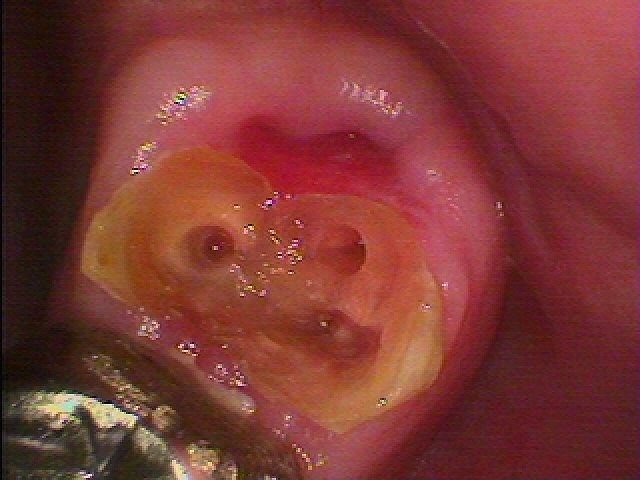

このようにファイバーコアにて支台築造を行っています

セレックセラミッククラウンにて審美的にもきれいに仕上げました